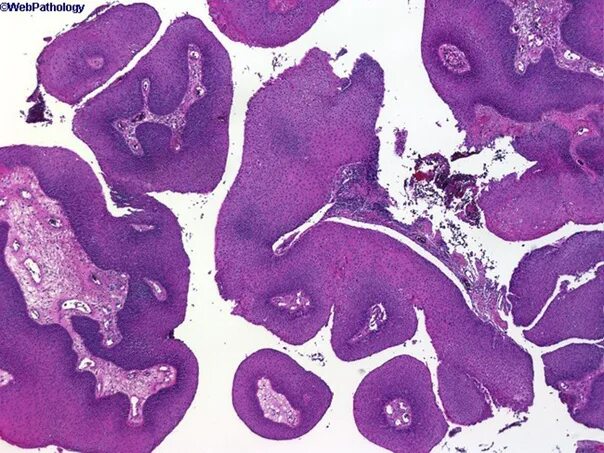

Папиллома гистология